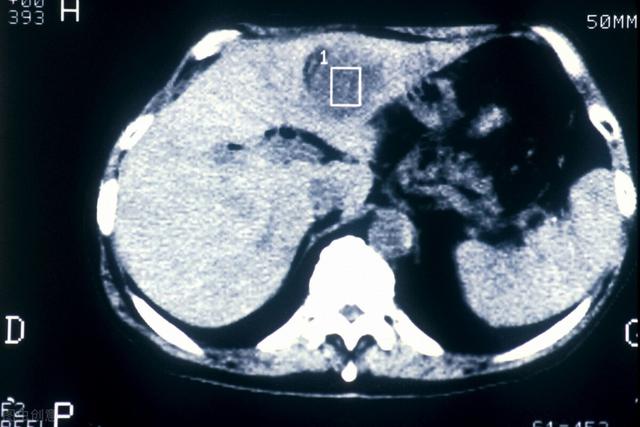

- 肝臓の超音波検査で肝臓に腫瘍が見つからない場合、または腫瘍の性質が判断できない場合、αフェト蛋白の上昇は肝細胞癌の可能性を強く疑わせる。さらに肝臓のCTを行うこともある。強化CTは肝臓腫瘍の特定に比較的優れているので、すぐに肝臓の強化CTをお勧めします。

上記の2番目の「肝がんの原因」を避けることに加え、40歳以上の人は、腹部超音波検査⏫とα-フェトプロテインの値を定期的にチェックする必要がある。